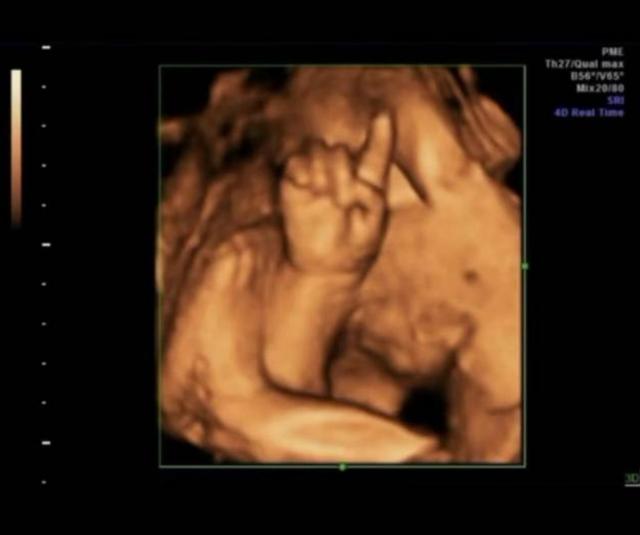

小夏這次去醫院做四維(超音波成像),通過屏幕顯示出來肚子裡的小傢伙正在擺弄著手勢,小夏仔細看了看,好像是數字「4」,她立刻拿出以前做四維的照片給醫生看。

原來小夏每一次做四維她都把胎兒在子宮裡的情況照下來,加上這次正好四次,而每次四維顯示出來的胎兒都在子宮裡擺出不同姿勢和手勢,但是連在一起就非常像小朋友「數數」,因為四次四維圖象連在一起胎兒的手勢正好是數字「1234」。

子宮裡黑乎乎的,胎兒周圍都是羊水,除了臍帶什麼都沒有,胎兒怎麼玩遊戲呢?其實胎兒的玩具就是臍帶,就是因為繞來繞去才有了臍帶繞頸,還有的胎兒會玩自己的手指,所以小夏看見自家寶寶在「數數」可能也是胎兒自娛自樂呢!